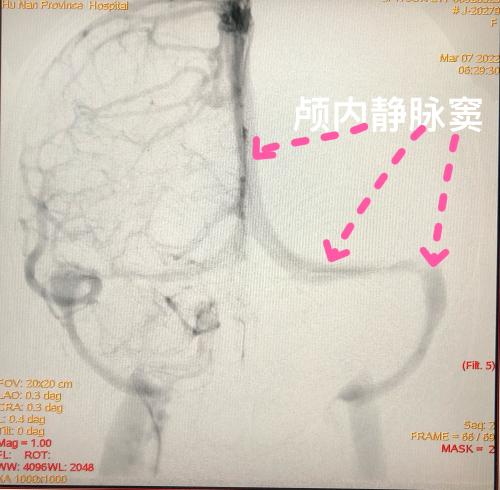

3月7日凌晨3时,张女士被护送至捷克论坛 介入血管外科一病区。副主任医师康超文、黄江在详细问诊评估后,立马启动绿色救治通道。在完善术前准备后,张女士被护送至介入手术室。术中脑血管造影提示,患者颅内静脉窦血流部分恢复,考虑血栓抗凝治疗后自溶。不幸中的万幸,抗凝治疗及时,张女士暂时无需进一步行介入碎栓取栓手术。通过护理团队的术后精心护理,张女士神志意识清楚,肌力正常,诉头痛也明显缓解。目前,张女士恢复良好,即将出院。